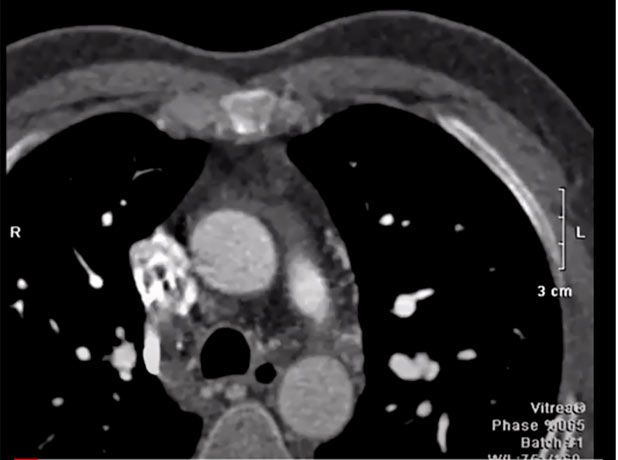

Image projections in CTA

Mohamed Gibreel , FEBR (Fellowship of Egyptian Board of Radiology ) Cardiac imaging consultant at Aswan heart center -Magdi Yacoub Foundation , Egypt